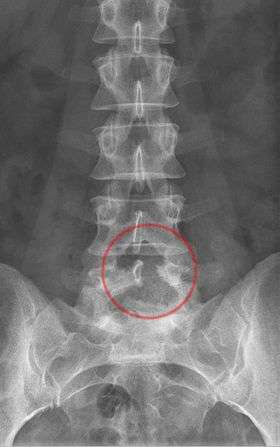

![]() Radiograph of the lumbar spine after hemilaminectomy of the fifth lumbar vertebra | |

A laminotomy is an orthopaedic neurosurgical procedure that removes part of a lamina of the vertebral arch in order to decompress the corresponding spinal cord and/or spinal nerve root.

This was originally performed as a hemilaminectomy, consisting in the removal of either the left or right half of the lamina, but is now more commonly carried out as the removal of a portion of both sides of the lamina (while retaining the rest to preserve vertebral stability as much as possible). Laminotomy is also often accompanied by facetectomy.